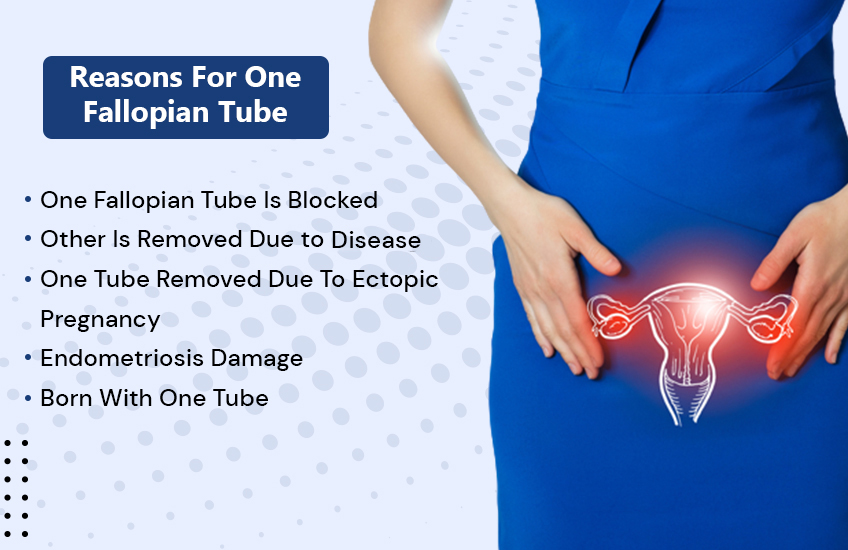

Fallopian Tube Pregnancy Symptoms

Blocked Fallopian Tubes Causes Symptoms And Treatment

Blocked Fallopian Tubes Symptoms Causes And Treatment

FTR Symptoms And Causes Of Blocked Fallopian Tubes Fibroid